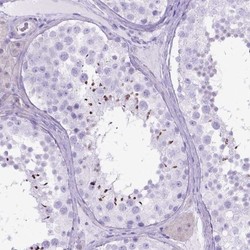

Supportive validation

- Main image

- Experimental details

- Immunohistochemistry: ARL9 Antibody [NBP2-49679] - Staining of human testis shows cytoplasmic positivity in spermatids.